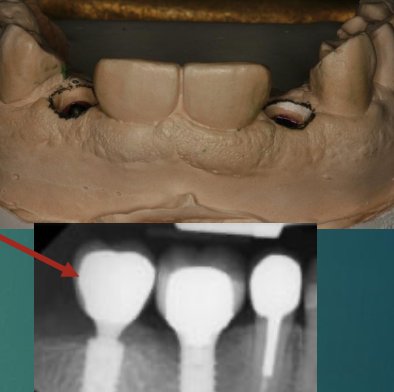

What are your next steps after the lab returns the master cast with full contour wax up?

Review the position and angulation of implant on cast

Locate screw access channel

Select abutment: screw-retained or cement retained

What will stone model contouring do?

Create an appropriate emergence profile for the restoration to create a “natural tooth” shape. It’ll help with hygiene and allow for adequate soft tissue support around the restoration

Contouring should allow ______ soft tissue between implant restoration and adjacent tooth

1 mm

Use carver to remove stone following the outline drawn on the model

Completed contouring. The cervical area has been expanded to allow for a “natural tooth” design

Emergence profile